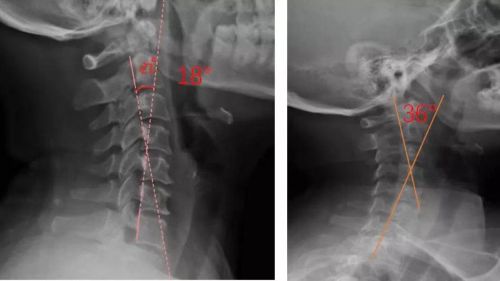

患者適配前后側位X光,佩戴前18°,適配后36°

我們通過對頸部進行光學掃描與頸椎側位X光檢查,測量頸椎曲度,由專業矯形器師結合患者的情況設計個性化頸椎枕,部分或全部3D打印工藝制作完成,矯正頸椎的生理曲度。患者適配后拍攝X光片,做到精準矯正與治療,避免使用不適和矯枉過正。

對于頸椎病患者,合理設計的頸椎枕,能夠緊密適合頸椎,矯正頸椎生理曲度;再根據頸椎曲度改善情況,隨時間慢慢調整3D打印頸椎枕曲度,使變直的頸椎逐漸形成正常的生理曲度,改善頸肩痛的癥狀。